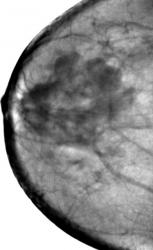

Случай 3.   Профилактическая маммография.  Рак молочной железы в виде "узлового образования".

ИзображениеИзображениеИзображениеИзображение

"Узловое образование", состоящее из нескольких опухолевых узлов, неоднородной структуры, с неровными, нечеткими, полициклическими контурами. Пациентка направлена в онкологический диспансер, взята на учёт, прооперирована.